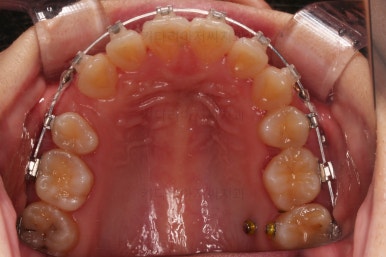

부산연산동교정치과 치료 종료 시의 모습이에요.

삐뚤한 치열도 가지런해졌고 2급 부정교합도 정상교합으로 맞춰졌어요.

튀어나와있던 앞니도 좋아졌고, 과개교합도 개선이 되었어요.

전후 사진을 비교해 보겠습니다.

전후 사진을 나란히 놓고 비교해 보면 굉장히 많이 좋아진 것을 볼 수 있으실거에요.

웃을 때의 치아의 위치를 보면 뒤로 들어간 것을 볼 수 있고, 이 영향으로 입매도 매우 예뻐졌고 편안해졌어요.

교합이나 치아배열의 모습도 좋아졌고요.

특히 관리가 힘들어 썩었던 치아도 충치치료 없이 발치교정할 수 있었고요.

남아있는 충치는 치료해야 되지만 교정치료는 잘 마무리 되었어요.